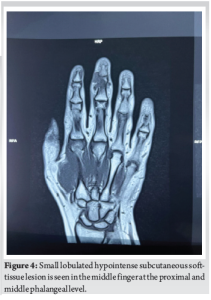

Plain radiographs of the right hand showed soft-tissue swelling (Fig. 3). Given the clinical suspicion, an MRI was performed (Fig. 4), revealing a small lobulated T1 and T2 hypointense subcutaneous soft-tissue lesion in the middle finger at the proximal and middle phalangeal level, extending between the flexor tendon and middle phalanx, measuring approximately 16 × 14 × 10 mm (CC × TR × AP), with surrounding soft-tissue edema. No evidence of bony infiltration was noted. The features were suggestive of a benign soft-tissue lesion (?TGCT). A small focal vascular ectasia was also noted in the index finger, measuring approximately 9 × 5 mm.